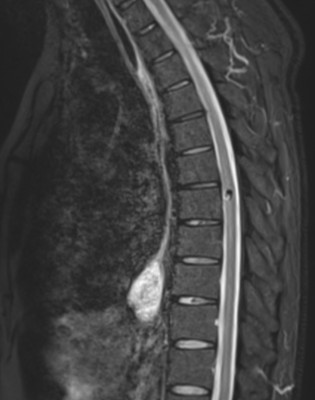

Resonancia Magnética de Columna

Envíado por Dr. José Rafael Chang Calero